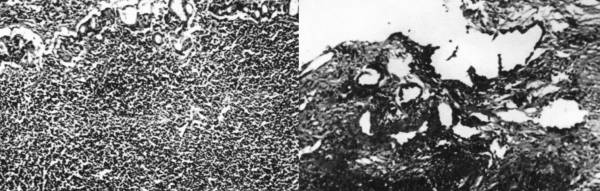

The pathologic examination of the endoscopic biopsies showed intestinal metaplasia and a dense lymphocytic infiltration of the mucosa giving the impression of a lym- phoma. In a particular tissue fragment, anomalous adeno- matous malformations with dysplastic epithelium were noted, suggesting  the  existence  of  a  gastric  adenocarci- noma (Figure 1).

2 fig 1